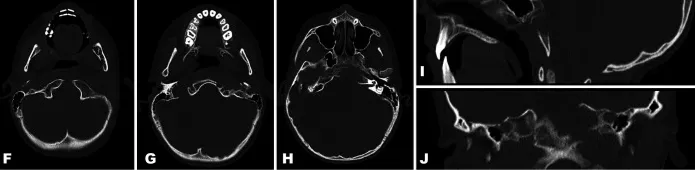

术前CT:左侧岩骨及斜坡骨质存在骨溶解性病灶